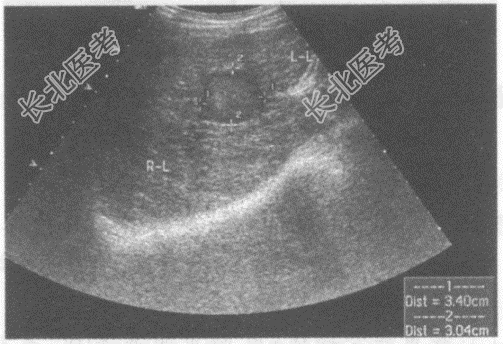

- 单项选择题临床资料:男性患者, 66岁;自述消瘦、腹胀不适; 患慢性乙型肝炎20年,

化验检查: AFP明显增高。

超声综合描述:肝表面不平, 肝回声不均,肝中裂增宽, 三支肝静脉变细,门静脉内径1.4cm, 左叶可见3.4cm×3.0cm中等回声区,周边有晕, CDFI:中等回声周边可见血管绕行。见下图及彩图。

超声提示: A、肝囊肿合并感染

B、肝腺瘤

C、肝硬化肝癌

D、肝血管瘤

E、肝脓肿